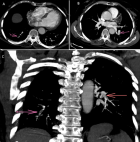

Diagnostic assessment: laboratory investigations on admission revealed a normal complete blood count with white blood cells at 6470 cells/mm3 (normal 4000-10000/mm3), hemoglobin at 12.7 g/dL (normal for women 12-16 g/dl), and platelet count at 176000 cells /mm3 (normal 150000-400000/mm3). Coagulation studies showed a prothrombin time of 99% with an activated partial thromboplastin time ratio of 1.00. Notably, fibrinogen was decreased at 1.8 g/L (normal 2-4 g/L). D-dimers were markedly elevated at 11.63 mg/L. Renal function was normal with creatinine at 4.95 mg/L (normal for women 5.07-11.1 mg/L) and urea at 0.32 g/L (normal 0.15-0.45 g/L). Liver enzymes were within normal limits: AST at 22 U/L (normal 5-34 U/L), ALT at 14 U/L (normal 0-55 U/L) with a normal serum lipase level of 12 UI/l (normal < 60U/l). Creatine kinase was mildly elevated at 256 U/L (normal for women 29-168 UI/l). C-reactive protein was normal at 3.93 mg/L (normal 0-5 mg/L). High-sensitivity troponin was within normal limits at 1.9 ng/L (<26 ng/l), and NT-proBNP was at 29.7 pg/mL. The electrocardiogram showed no abnormalities (Figure 1) and the chest X-ray was unremarkable with no infiltrates, pleural effusion, or cardiomegaly. Transthoracic echocardiography showed a non-dilated right ventricle with good systolic function. There was no paradoxical septal motion, right ventricular pressure overload, signs of pulmonary hypertension, or any other echocardiographic evidence of acute cor pulmonale. No visible thrombus was detected in the pulmonary artery. The left ventricle was non-dilated with good systolic function (ejection fraction of 60%) and left ventricular filling pressures were normal (Figure 2). Given the respiratory symptoms and markedly elevated D-dimers, a computed tomography pulmonary angiography (CTPA) was performed, which revealed segmental pulmonary embolism in the right posterobasal segment and left lower lobe without signs of right ventricular strain (Figure 3). Lower limb venous doppler ultrasound did not reveal any deep vein thrombosis. An etiological workup was performed to rule out underlying malignancy. Cerebral CT angiography and cervico-thoraco-abdomino-pelvic contrast-enhanced CT scans showed no abnormalities, and tumor markers were negative. A formal thrombophilia screening was not performed, as this was a first episode of venous thromboembolism clearly linked to a temporary and identifiable risk factor.

Figure 3: (A,B,C) computerized tomography pulmonary angiography images demonstrating segmental pulmonary emboli in the right posterobasal segment and the left lower lobe (arrows)